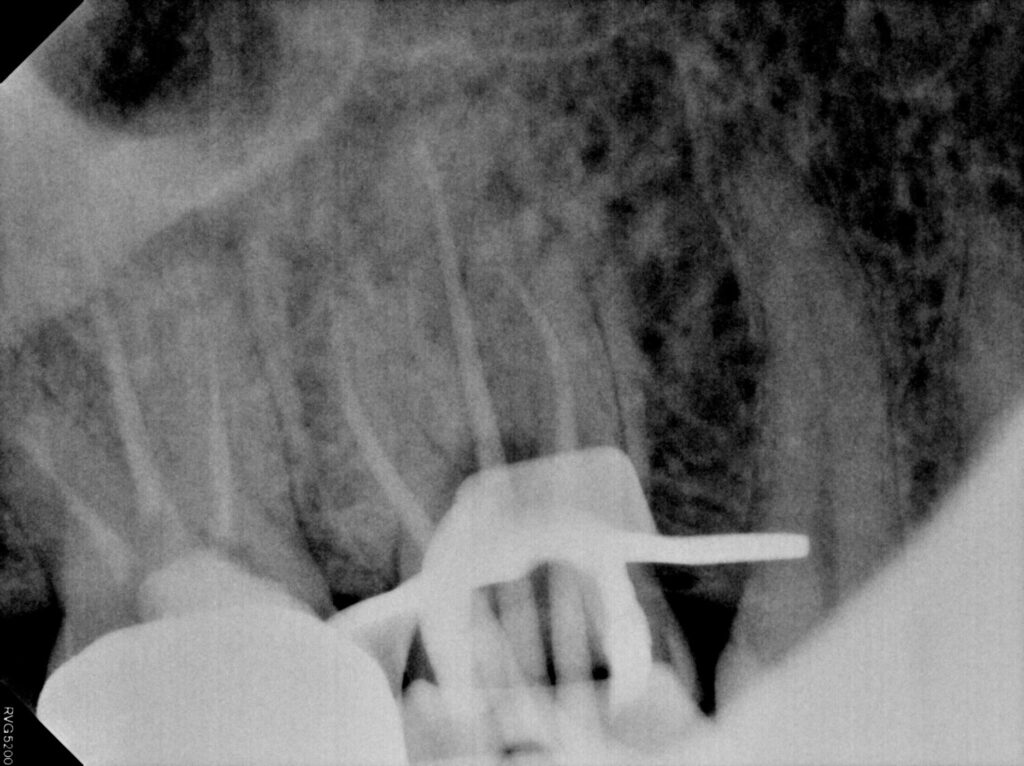

역시 남은 치질이 많이 없었는데요.

치아의 테두리는 남아 있어

재신경치료를 진행하였고

염증과 고름주머니, 통증이 사라져

단단한 재료로 메워 크라운을 진행하도록

준비하였습니다.